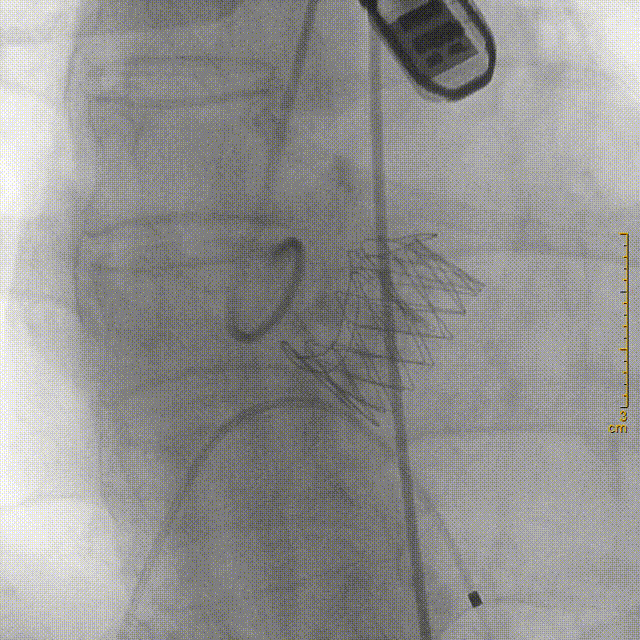

严重钙化使瓣膜形态未完全展开

球囊扩张后,瓣膜形态完美,超声复查无瓣周漏,冠脉开口无堵塞